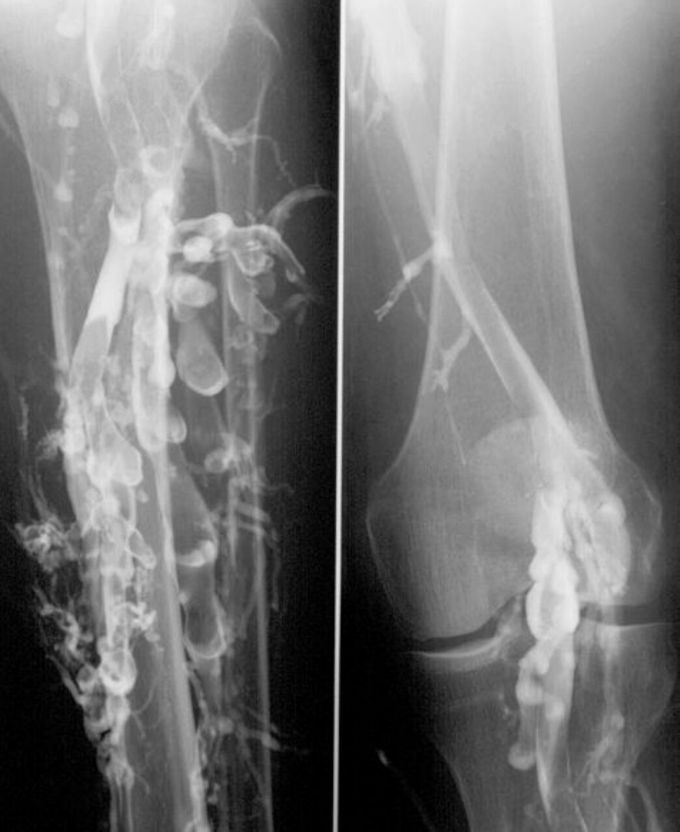

Phlebography in a patient with deep venous thrombosis (DVT)